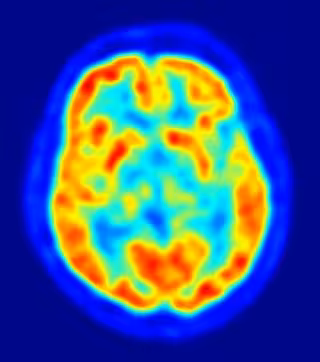

Estudian la relación entre el sistema inmune del cerebro y el Alzheimer

Investigadores del Grupo de Fisiopatología de la Enfermedad del Alzheimer del área de Neurociencias del Instituto de Biomedicina de Sevilla (IBIS) están analizando cómo retrasar las consecuencias del Alzheimer mediante el estudio de las células microgliales, que forman parte del sistema inmune del cerebro y que se activan de forma "excesiva" con la aparición de la enfermedad.

El objetivo es esclarecer si la respuesta inmune puede estar implicada en la degeneración de las células neuronales y con ello diseñar una posible terapia para retrasar los efectos de la patología. En este sentido, los expertos emplean técnicas de bioquímica, biología molecular y biología celular, es decir, cultivos de tejidos, animales transgénicos, muestras humanas y preparando nuevos animales para ver cómo se comporta el sistema inmune cerebral.